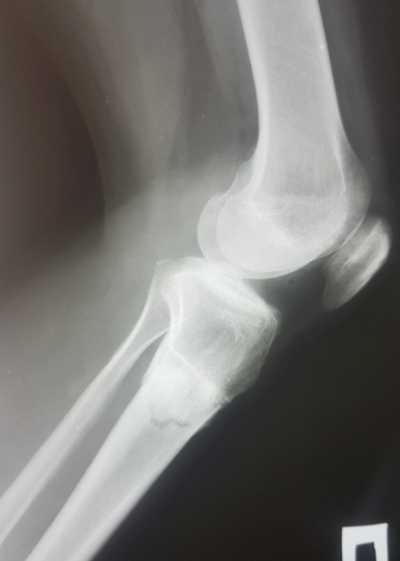

Рентген снимки через 1,5 месяца с момента снятия аппаратов